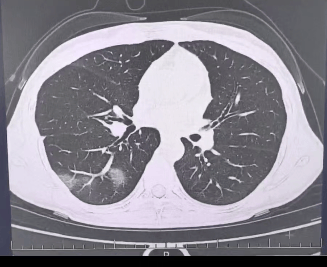

检查结果显示opensea,

程女士的好几叶肺

都出现了“白肺”现象opensea,

指间血氧饱和度只有 88%opensea,

血心肌酶谱、肌钙蛋白的指标、肝功能的指标

也出现了明显的异常opensea。

确诊流感(重型)opensea!

图源:杭州市第三人民医院微信公众号